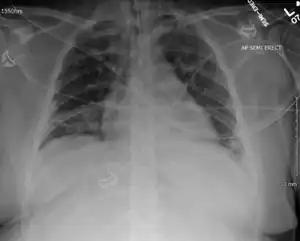

Transmission electron micrograph of enterovirus D68 virus particles[17] -